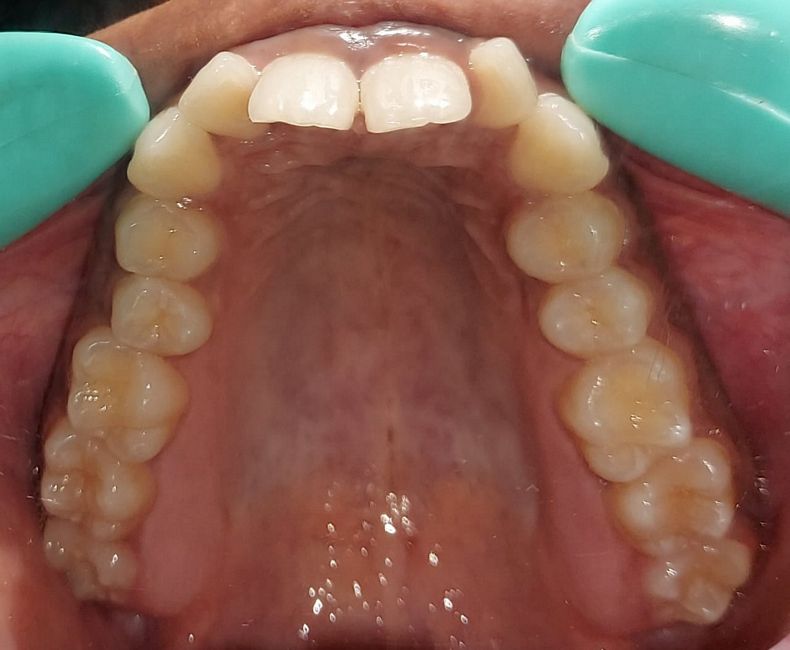

Case No: 24

Malocclusion Type: Class I Malocclusion (Retreatment).

Mechanics: Aligners.

Treatment: Class I Malocclusion with Spacing in upper and lower anteriors treated with Clear Aligners.